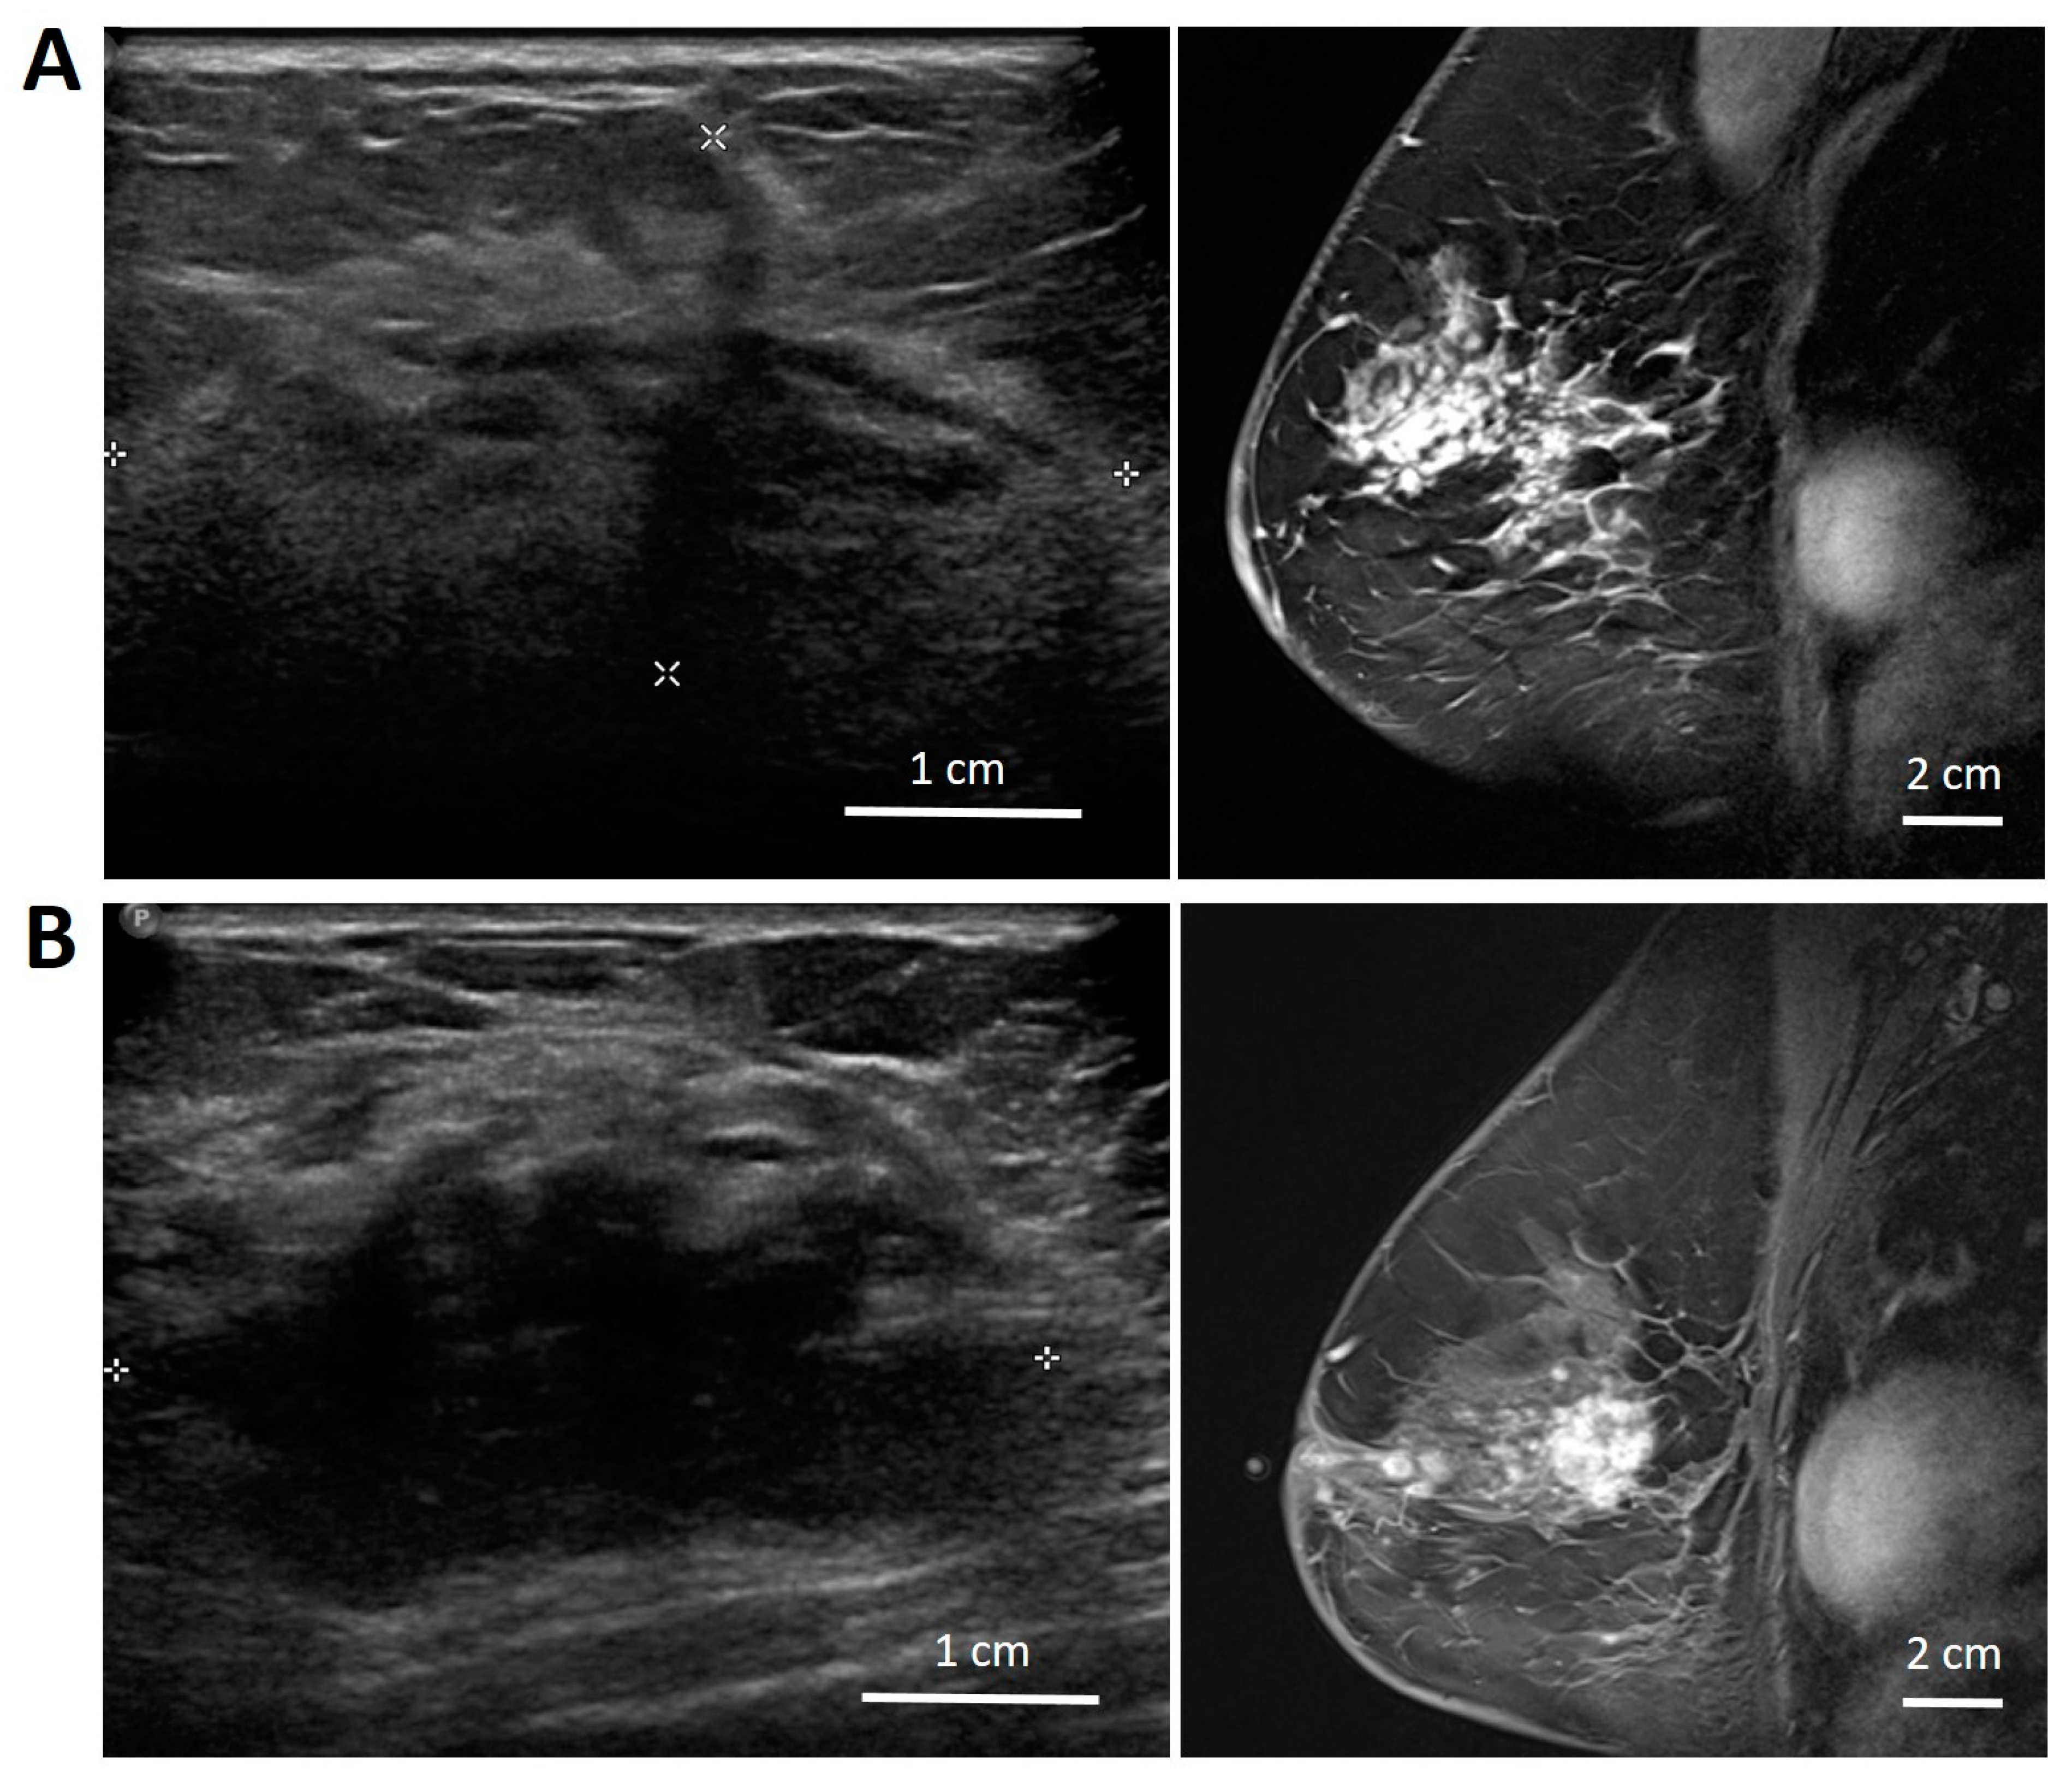

Regarding the first patient (patient number 4 in Figure 3), the class score of prediction was close to 0, which means that the radiomics features were borderline (indeterminate) and did not strongly favour either responders or non-responders. In the second patient (patient number 12 in Figure 3), the tumour had a poorly defined border in ultrasound (Figure 4) and MRI, and it was possible that the delineated region of interest may not have accurately included the tumour plus a 5 mm margin. This could have influenced the accuracy of prediction. In the third patient (patient number 18 in Figure 3), the tumour was very close to the Cooper’s ligament. The region of interest was the tumour with a 5 mm margin, which in this case included the Cooper’s ligament. This might have affected the prediction accuracy, as the imaging parameters of the Cooper’s ligament can be very different from the usual 5 mm margin of adjacent breast tissue.

Figure 4.

Example of an ultrasound (left) and MRI (right) images of patient 12 (A) and patient 19 (B) showing a tumour with heterogeneous, distorted, and poorly defined boundary structures.